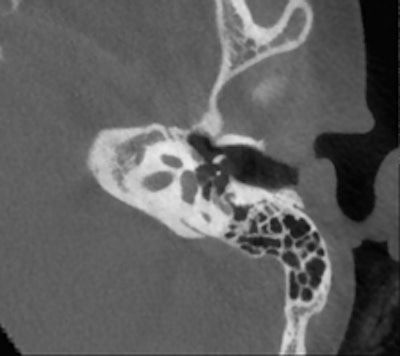

Conebeam CT double oblique reformation of the right temporal bone of a 12-year-old child with conductive hearing loss on the right side, showing a focus of otospongiosis anterior to the footplate. Images courtesy of Dr. Bert De Foer."If the problem is related to conductive hearing loss, then it is most likely to be in the middle ear, in the ossicles, and this requires a CT scan or a conebeam CT. But if the hearing loss is sensorineural, you need to use MRI," stated De Foer, adding that the clinical history of the patient and the clinical examination also will help in choosing the appropriate imaging technique.

He is an advocate of conebeam CT, which is growing in popularity, and recounted the advantages of conebeam CT over conventional CT. He said that he previously conducted all temporal bone imaging on a multidetector-row CT, but he now uses conebeam CT far more frequently. It is different because he uses a flat-panel detector, which provides a high resolution, he explained. Images scan at 0.1-mm resolution, whereas multidetector-row CT scans at 0.5 mm to 0.6 mm.

Several of De Foer's patients were initially scanned on multidetector-row CT and returned postsurgery to receive a conebeam CT. The detail on a conebeam CT is much greater, and the dose is also eight to nine times lower with conebeam in our study of it, he said.

"The level of detail of the ossicular chain is better. For example, the footplate detail is clearer," he said. "The facial nerve running through the middle ear has a bony coverage which is hardly visible on multidetector CT but is very visible on a cone-beam; likewise, the bony covering of the superior semicircular canal, which is important in the Tullio phenomenon."

De Foer also described how conebeam CT is particularly suitable for otosclerosis. This pathology relates to a demineralization of the bone in the inner ear, which prevents the stapes from conducting sound. Conebeam CT shows this in more detail than multidetector-row CT, especially in the evaluation of the footplate.